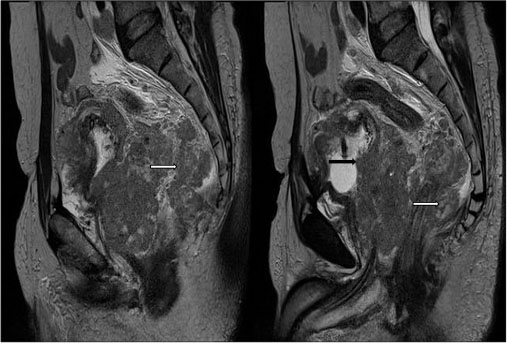

MRI lumbosacral spine with pelvis revealed multiple well-defined variable sized round to oval lesions in lumbar vertebrae, sacrum and pelvic bones, appearing hypointense on T1-weighted image and T2-weighted image (T2WI) and hyperintense on Short tau inversion recovery (STIR) [Figure 3]. Ill-defined T2WI hyperintense fluid collection was noted in the retroperitoneum on right side likely lymphedema due to lymphatic obstruction. Prostate was enlarged with hypointense lesion in peripheral zone with extra-prostatic spread on right side with involvement and thickening of right seminal vesicle with extension in right perirectal fat [Figure 4] and [5].

| Figure.5:65-year-old male complaining of increased frequency of micturition, anorexia and weight loss due to small cell carcinoma of prostate. Sagittal T2-weighted showing enlarged prostate with urinary bladder invasion (black arrow) and extra-prostatic spread on right side with involvement of right peri-rectal fat (white arrow)